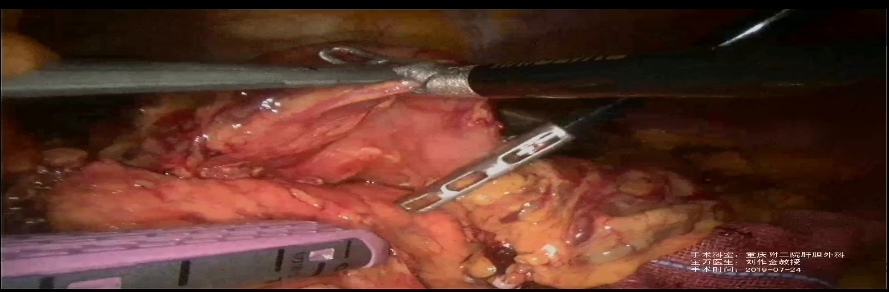

7月24日,在《中華普通外科雜志》主辦的“胰動(dòng)我心”胰腺外科周手術(shù)演示會(huì)上���,重慶醫(yī)科大學(xué)附屬第二醫(yī)院肝膽外科副主任劉作金教授�,以手術(shù)直播的形式完成了一臺(tái)腹腔鏡胰十二指腸根治術(shù)手術(shù)�����。重慶西山科技股份有限公司(以下簡(jiǎn)稱“西山科技”)一次性使用腔鏡吻合器(升級(jí)版)在手術(shù)中共使用三次。

此臺(tái)手術(shù)面向全國(guó)直播��,有上萬業(yè)內(nèi)人士同時(shí)觀看���。手術(shù)直播過程中,西山科技吻合器完成了腔鏡吻合器紫釘(不等高釘)橫斷胃體����,腔鏡吻合器白釘(平釘)橫斷空腸以及腔鏡吻合器藍(lán)釘(平釘)做胃空腸吻合,三次吻合效果非常完美���。劉作金教授稱贊西山科技的吻合器“相當(dāng)?shù)膎ice”����,并呼吁支持國(guó)產(chǎn)醫(yī)療器械���。